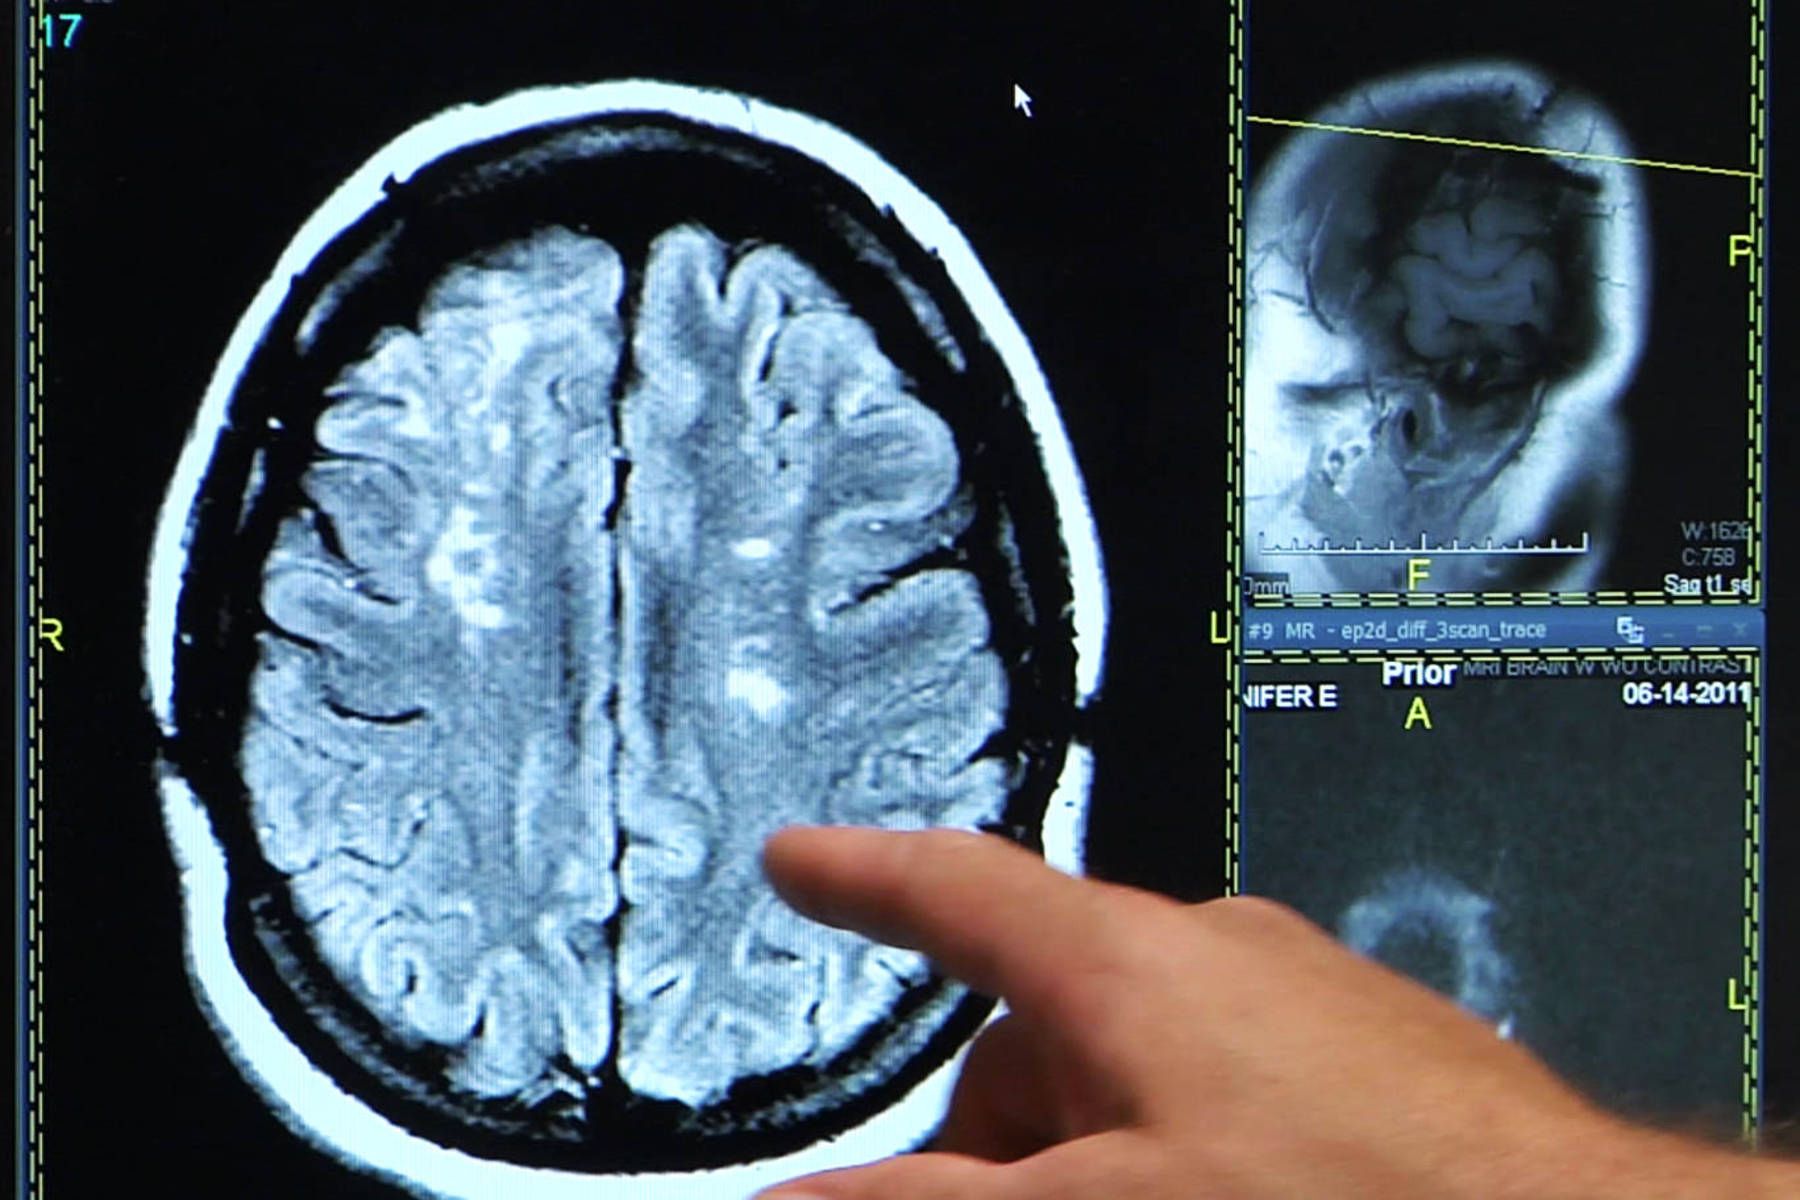

Duminică, tromboliză efectuată în premieră în județul Galați. O pacientă ajunsă la Spitalul Clinic Judeţean de Urgenţă „Sf. Apostol Andrei” upă ce suferise un accident vascular cerebral (AVC) a fost supusă unei proceduri de tromboliză intravenoasă.

Pacienta de 68 de ani supusă duminică intervenţiei de tromboliză suferise de curând un AVC. Procedura a fost efectuată de o echipă de medici în cadrul Unităţii de Primire Urgenţe (UPU) a Spitalului Judeţean din Galaţi. În cadrul tratamentului, substanţa injectată intravenos, prin intermediul unei perfuzii, a distrus un cheag format într-un vas de sânge din creierul femeii. „Din fericire, pacienta s-a prezentat la UPU în fereastra terapeutică cerută de acest tip de intervenţie. Concret, este vorba de primele 4,5 ore după suferirea AVC-ului. Aceasta a fost prima intervenţie de acest tip efectuată la Spitalul Clinic de Urgenţă din Galaţi. Procedura a decurs conform planului, iar pacienta se recuperează în prezent, starea sa fiind stabilă din punct de vedere clinic”, a precizat Alina Dobrea, managerul Spitalul Clinic de Urgenţă Galaţi.